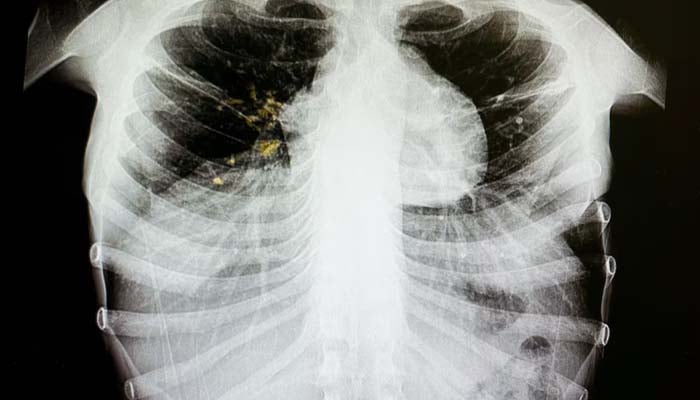

Tuberculosis is an infectious disease that often affects the respiratory system, but it can also affect other parts of the body.

It can be rapidly transmitted when an infected person coughs, sneezes and spits; however, it can be treated with antibiotics.